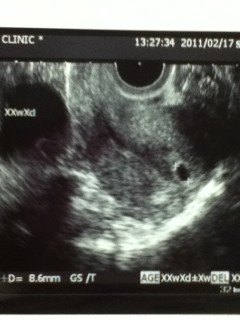

妊娠発覚してから初めて病院に行ったら、まだ4週だったため胎のう確認出来ませんでした。先生には、来週も確認出来なかったら騒がなアカンって言われてドキドキしていました。1週間にまた診てもらったら確認出来ました。

先生が、おるおるーって騒いでて、ビックリさせんなーって言われました。笑。それはこっちも同じです。とりあえず第一段階突破ってところですね。

胎のうは8.6mmで、5wだと思ってたけど先生は5w3dと書き込んでいました。

エコー写真

あなたのエコー写真と比べてみては...